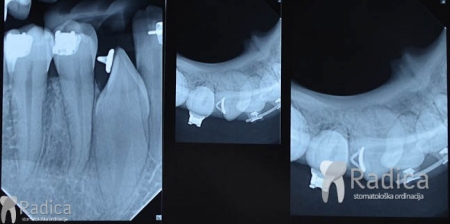

U sljedećem primjeru su se na mjesto donjih ekstrahiranih prvih molara stavili dentalni implantati prije ortodontske terapije (rad dr. Gorana Radice) i ujedino su služili za pojačenje sidrišta tijekom ortodontske terapije. Nakon ortodontske terapije estetski su se preoblikovali sjekutići i napravile nove krunice (također rad dr. Gorana Radice).